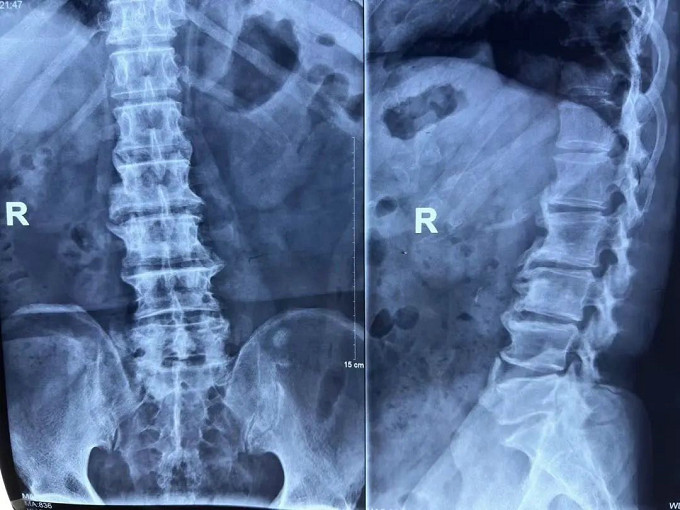

患者影像资料:

术前

X线片

可以明显的看出,患者术前椎间盘突出压迫到了神经。